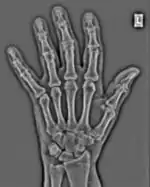

FFTs can also be calculated in two-dimensions to give results such as those in Figure 1.27. Since Fourier analysis generates results in terms of both positive and negative spatial frequencies, these can be plotted in the form of a 2D image so that the maximum frequency lies at the origin and those for the horizontal and vertical directions are shown increasing towards that origin. The modulation at different spatial frequencies is represented using a grey-scale. Low frequency bands can be seen along the horizontal axis in the figure, for example, representing the horizontal periodicity of image data from the fingers, while finer bands along the y-dimension are indicative of a periodicity of image data from the various metacarpophalangeal joints. Higher frequency features can also be seen running diagonally in this 2D-FFT, representative of the trabecular structure of the bones, for example.

The essence of this approach is that it can be used to produce a range of image processing effects by enhancing and/or suppressing features in the 2D-FFT and then converting the result back into the spatial domain using the IFT, as illustrated in Figure 1.28. Such image manipulations are considered in more detail in a later chapter. Note that the form of image processing demonstrated in the figure is for purely illustrative purposes and bears no direct medical significance.

![]() Fig. 1.28(a): A radiograph of the wrist. | ![]() Fig. 1.28(b): The wrist radiograph processed by attenuating periodic structures of size between 1 and 10 pixels. |

![]() Fig. 1.28(c): The wrist radiograph processed by attenuating periodic structures of size between 5 and 20 pixels. | ![]() Fig. 1.28(d): The wrist radiograph processed by attenuating periodic structures of size between 20 and 50 pixels. |